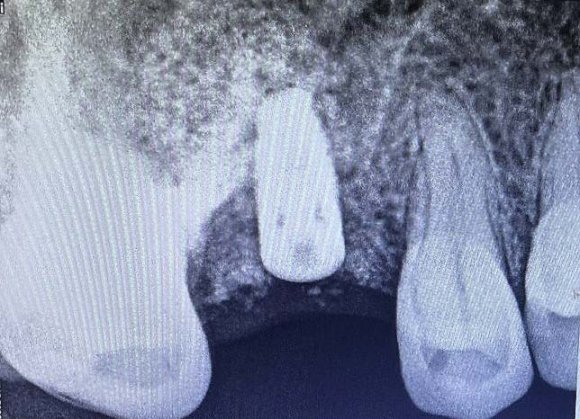

La comparaison des téléradiographies permet d'objectiver le redressement incisif mandibulaire et la distalisation molaire mandibulaire obtenue. Nous observons également le maintien des axes incisifs au niveau de l'arcade maxillaire.

On note un redressement incisif très important. En effet, l'axe incisif mandibulaire est passé de 112° à 90.3° en 6 mois. Une distalisation molaire de3 mma également été obtenue. Les axes incisifs maxillaires ont été maintenus, ce qui correspond parfaitement à notre objectif de départ. Grâce au bon redressement des axes incisifs et donc à une phase de décompensation pré-chirurgicale efficace, l'avancée mandibulaire a pu être suffisante et a permis de complètement corriger la classe II squelettique et dentaire.